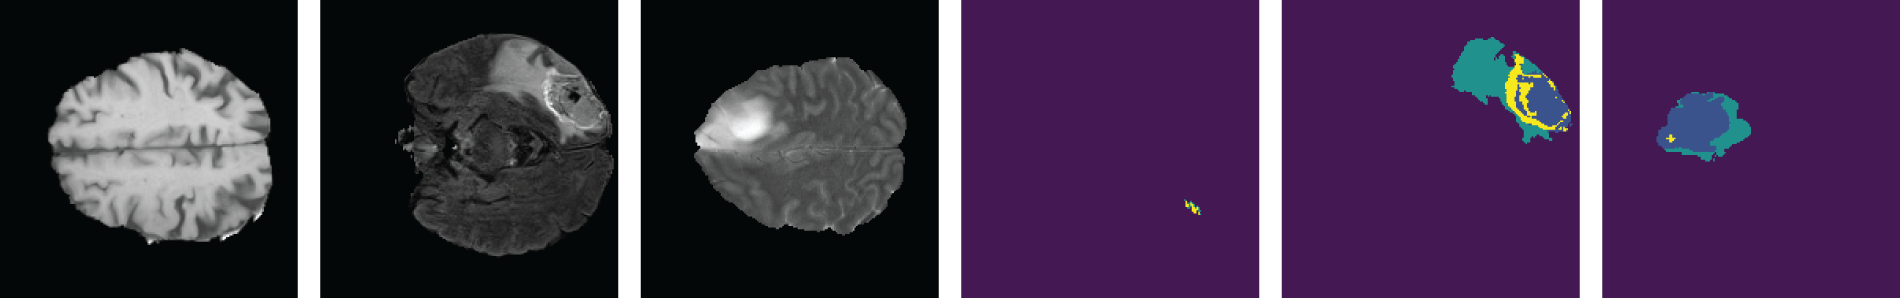

We used BraTS 2020 [25,26] for our research. This dataset has two classes: LGG and HGG. Two random MRI scans from the dataset are shown in Fig. 8. For a single patient, each dataset includes one ROI and four 3D MRI sequences (T1, T1-weighted, T2-weighted, and T2 Fluid Attenuated Inversion Recovery), all stored in Neuroimaging Informatics Technology Initiative (NIfTI) files. Each 3D volume also includes 150 2D MRI slices or images from various brain regions. The single slices are in single-channel grayscale format with a dimension of

Figure 8: BraTS dataset contains two classes. (a) HGG and (b) LGG

As we are working with two-dimensional images, it is essential to use 2D image data exclusively. We obtained the dataset from Kaggle, comprising 57,198 Hierarchical Data Format-5 (HDF5) files containing 2D images that had been preprocessed from MRI sequences. Each HDF5 file contains four distinct MRI sequences. Following this, we conducted image cropping along all margins to eliminate the non-informative black regions surrounding the brain MRI scans. This strategic cropping procedure was employed to eliminate extraneous areas and optimize the precision of our classification outcomes. After cropping the images, the dimension of the new images became

Figure 9: Samples from the dataset